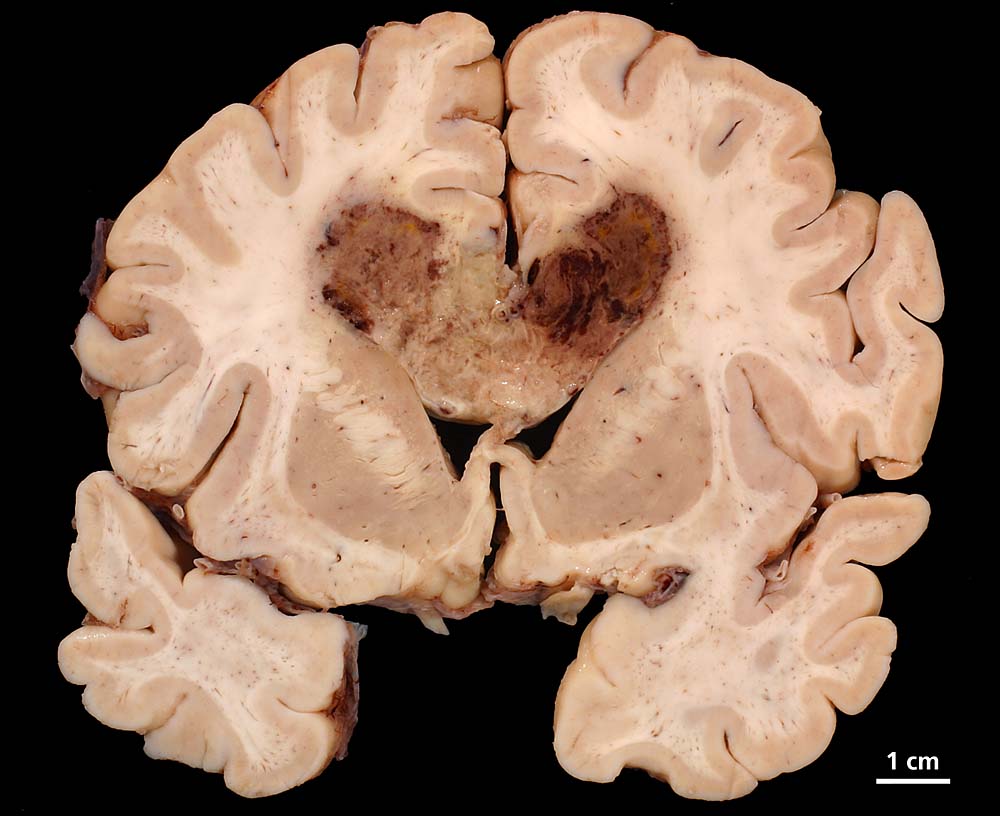

Glioblastoma multiforme

Bräunlich verfärbter "Schmetterlingsförmiger" Erweichungsherd im Bereich des corpus callosum.

Vor einem halben Jahr Wesensveränderung, Aphasie, psychomotorische Verlangsamung, Harninkontinenz. Computertomographisch Verdacht auf Glioblastoma multiforme im Bereich des Truncus corporis callosi. Einen Monat später zunehmende Verschlechterung des Allgemeinzustandes mit Fieber und Verdacht auf Aspirationspneumonie.